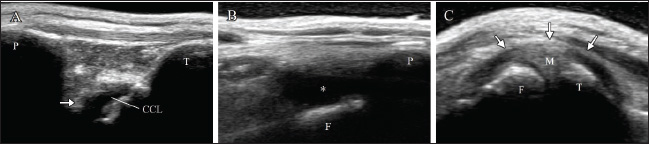

Radiography of the right stifle joint indicated infrapatellar fat pad signs and cranial tibial luxation (Fig. 1A). No obvious angular limb deformities were observed (Fig. 1A and D). Ultrasonography of the stifle joints (ARIETTA Prologue; Fujifilm Co., Japan; 18 MHz linear probe) revealed a complete CCLR, severe joint effusion, and medial buttress in the right stifle joint with no injury to the medial meniscus (Fig. 2A–C). Furthermore, partial CCLR and mild joint effusion were observed in the left stifle joint.

Fig. 2. Ultrasonography of the right stifle joint at the first visit. Complete rupture of the cranial cruciate ligament (arrow, A) and severe joint effusion (asterisk, B) can be observed. Although the medial buttress (arrow, C) can be visualized, the caudal horn of medial meniscus shows no damages (C). CCL=cranial cruciate ligament; F=femur; M=medial meniscus; P=patella; T=tibia.